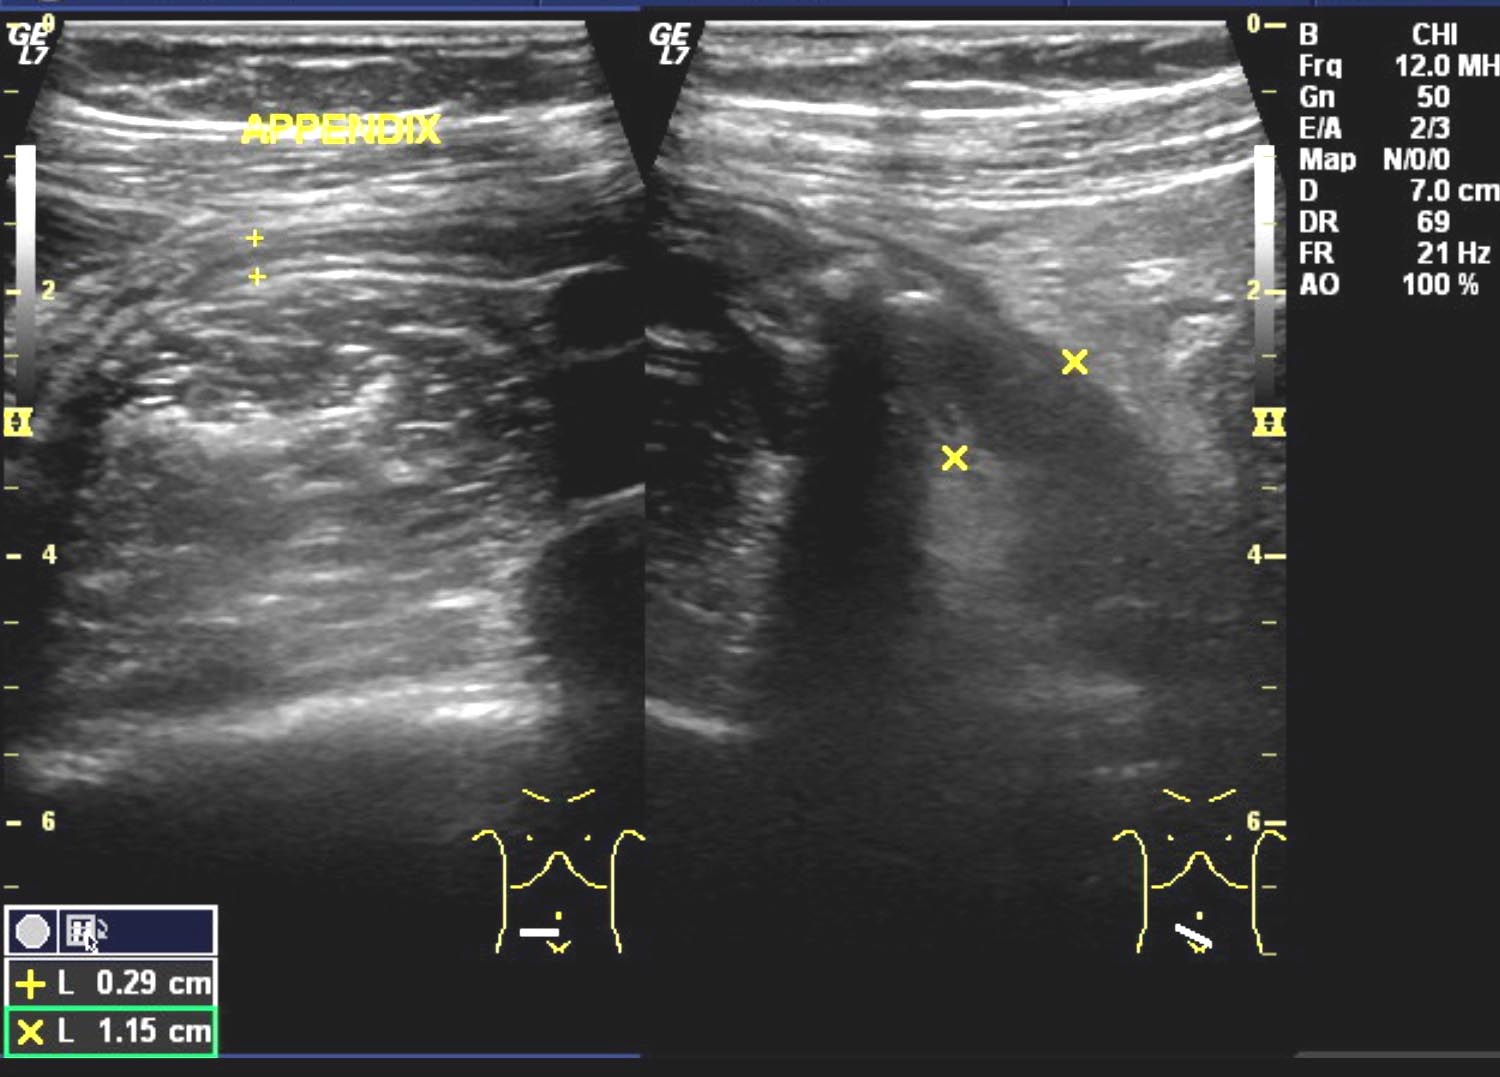

Acute Meckel's diverticulitis Radiology Case

Acute Meckel's diverticulitis Radiology Case Source: radiopaedia.org